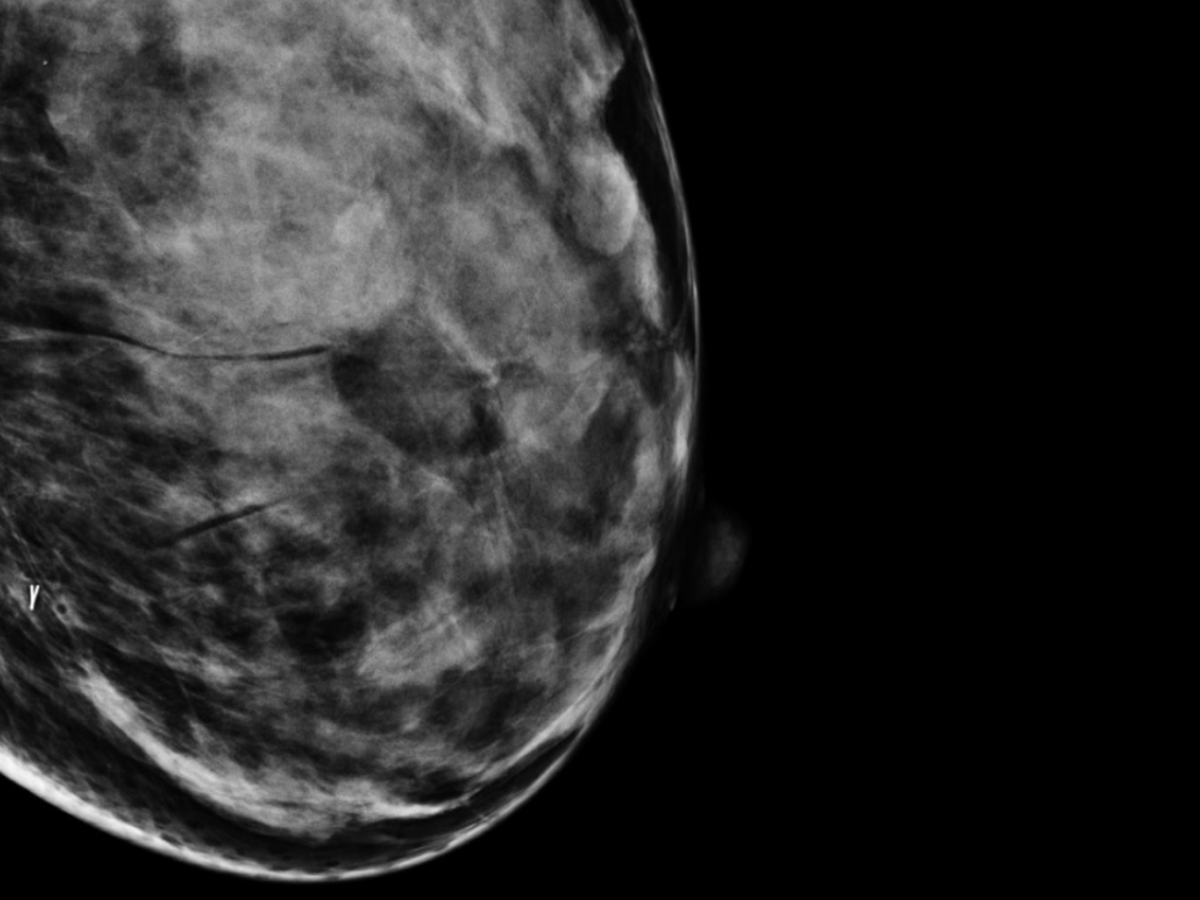

My name is Queen, I am am a disabled cannabis educator from DC whose lived in MD the majority of my life, I am 1/2 of Dispense Throne, lab technician and mother of an Autistic 13 year old and wife; in other parts of my life, I’m known as DQ and have dedicated the last 15 years of my life towards cannabis education, advocacy while in pursuit of a cannabis license in MD, this has involved doing lots of mutual aid and donations towards other folks who needed assistance from legal, personal and financial and recently I’ve been diagnosed with Stage 2b Infiltrating Ductal Carcinoma in Situ with a nuclear grade 2/3 tumor in my left breast.

Self Breast Exams find 40% of Breast Cancers that start with a lump

Breast Cancer timeline:

Original complaint of pain in breast: 2/10/23

Self-Breast Check: 11/10/24

Ultrasound and Mammogram: 12/17/24

Multi Site Biopsy: 12/16/24

Pathology & Surgical Referral: 1/9/25

Surgical Consultation for Lumpectomy: 12/21/25